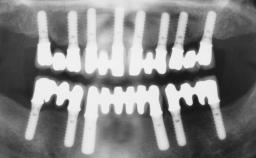

A fully edentulous 65-year-old woman was referred to our clinic for esthetic and functional dental rehabilitation. The patient presented with inadequate complete maxillary and mandibular prostheses, insufficient vertical dimension, and extensive tooth wear. The clinical examination and anamnesis showed no local or systemic contraindications, no signs or symptoms of bruxism, and an absence of smoking habits. The treatment proposed was implant placement in the mandibular interforaminal area and immediate loading with a fixed definitive prosthesis. A removable mucosa-supported complete prosthesis was indicated for the upper jaw, since its bone structure offered satisfactory retention and the financial condition of the patient disfavored a full-mouth implant-supported rehabilitation.

# of Implants 4

Loading Protocol Immediate

Retention Screw-retained, with 4 or more splinted implants Screw-retained, with 4 or more splinted implants